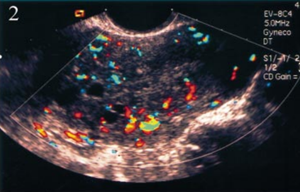

Các trường hợp có nghi ngờ lạc tuyến trong cơ tử cung trên nội soi đều được siêu âm màu và chụp cộng hưởng từ nhân để khẳng định chẩn đoán bởi các bác sĩ khoa chẩn đoán hình ảnh bệnh viện ĐHYD đảm nhận.

Siêu âm Doppler nghi Adenomyosis |